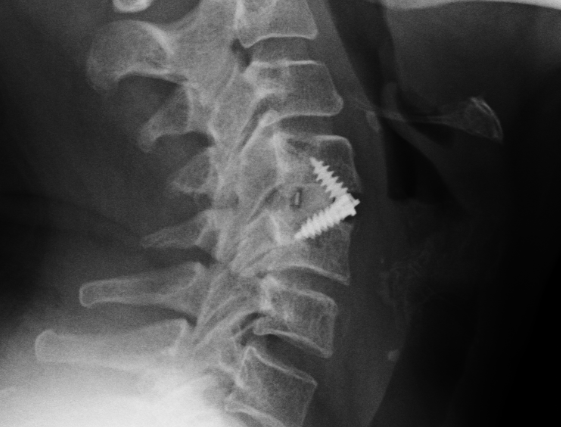

fusión intersomática a través de la caja atornillada

fusión intersomática sobre todo en la parte posterior de la caja (lo más frecuente)